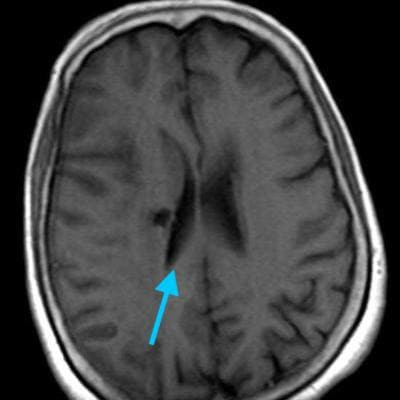

Внутричерепная гипотензия: КТ-исследования и их интерпретация

Раздел: Образы вокруг